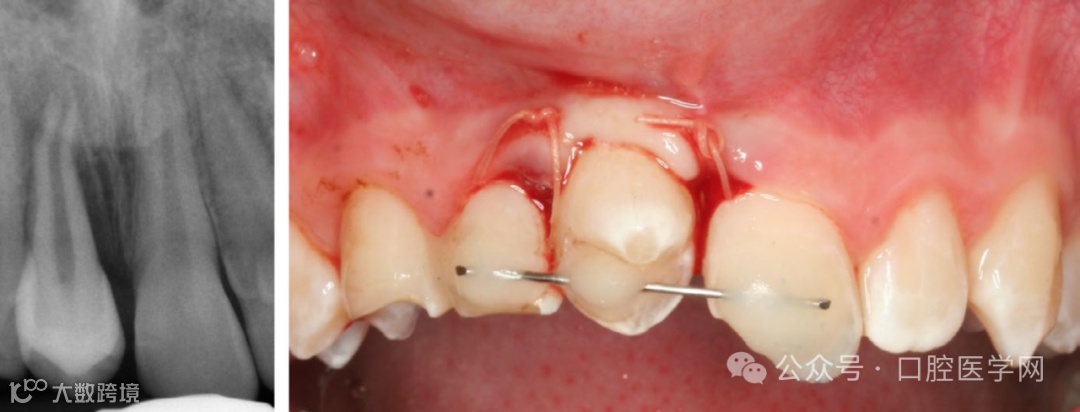

图2

13岁男孩的上颌前磨牙自体移植到因牙外伤缺失的门牙区。术后即刻临床和影像学视图。